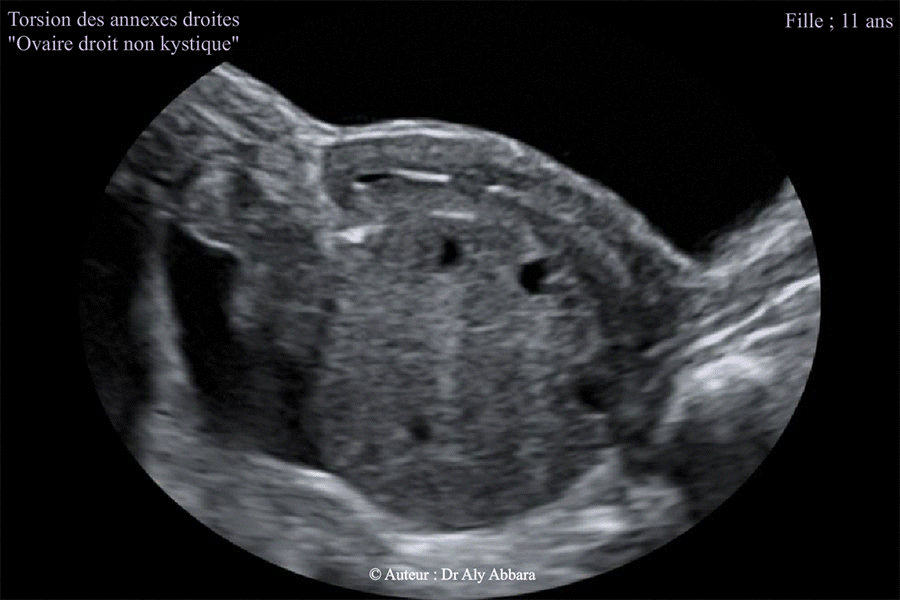

Torsion des annexes droites chez une fille de 11 ans - Aspect échographique de l'utérus et de l'ovaire droit

Images échographiques montrant une torsion des annexes utérines droites chez une fille de 11 ans (non encore réglée - pas de ménarche) - ovaire droit non kystique.

D'après le contexte clinique, il s'agit d'une torsion débutant 22 heures auparavant.

L'image échographique montre un ovaire droit augmenté de volume (73 cm3 contre 8 cm3 qui est le volume de l'ovaire gauche non tordu). On observe la présence des follicules antraux (de 2 à 5 mm de diamètre) dispersés au sein de cet ovaire et séparés par un stroma ovarien œdémateux et infiltré (cliniquement par le sang) et fort probablement nécrobiosé par une ischémie (silence Doppler couleur) due l'obturation mécanique des vaisseaux vascularisant normalement les annexes utérines (torsion de 720° à l'inverse des aiguilles de montre : du ligament utéro-ovarien ; du ligament large et du ligament lombo-ovarien droits).

La trompe droite qui individualisable sur cette image est augmentée de calibre ; infiltrée et ischémique (comme l'ovaire homolatéral).

Il existe aussi un petit épanchement pelvien, périannexiel droit (cliniquement : liquide péritonéal sanglant d'environ 100 cc de volume).